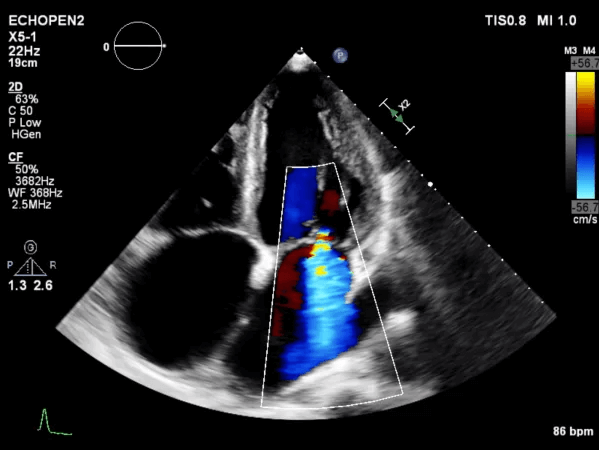

Transthoracic Echocardiogram

A transthoracic echocardiogram is an ultrasound that evaluates your heart's structure and function, providing detailed images to assess how well the heart muscle, valves, and chambers are working. It measures heart wall thickness, chamber size, and valve function, helping to detect any abnormalities. Doppler ultrasound is used to check blood flow.